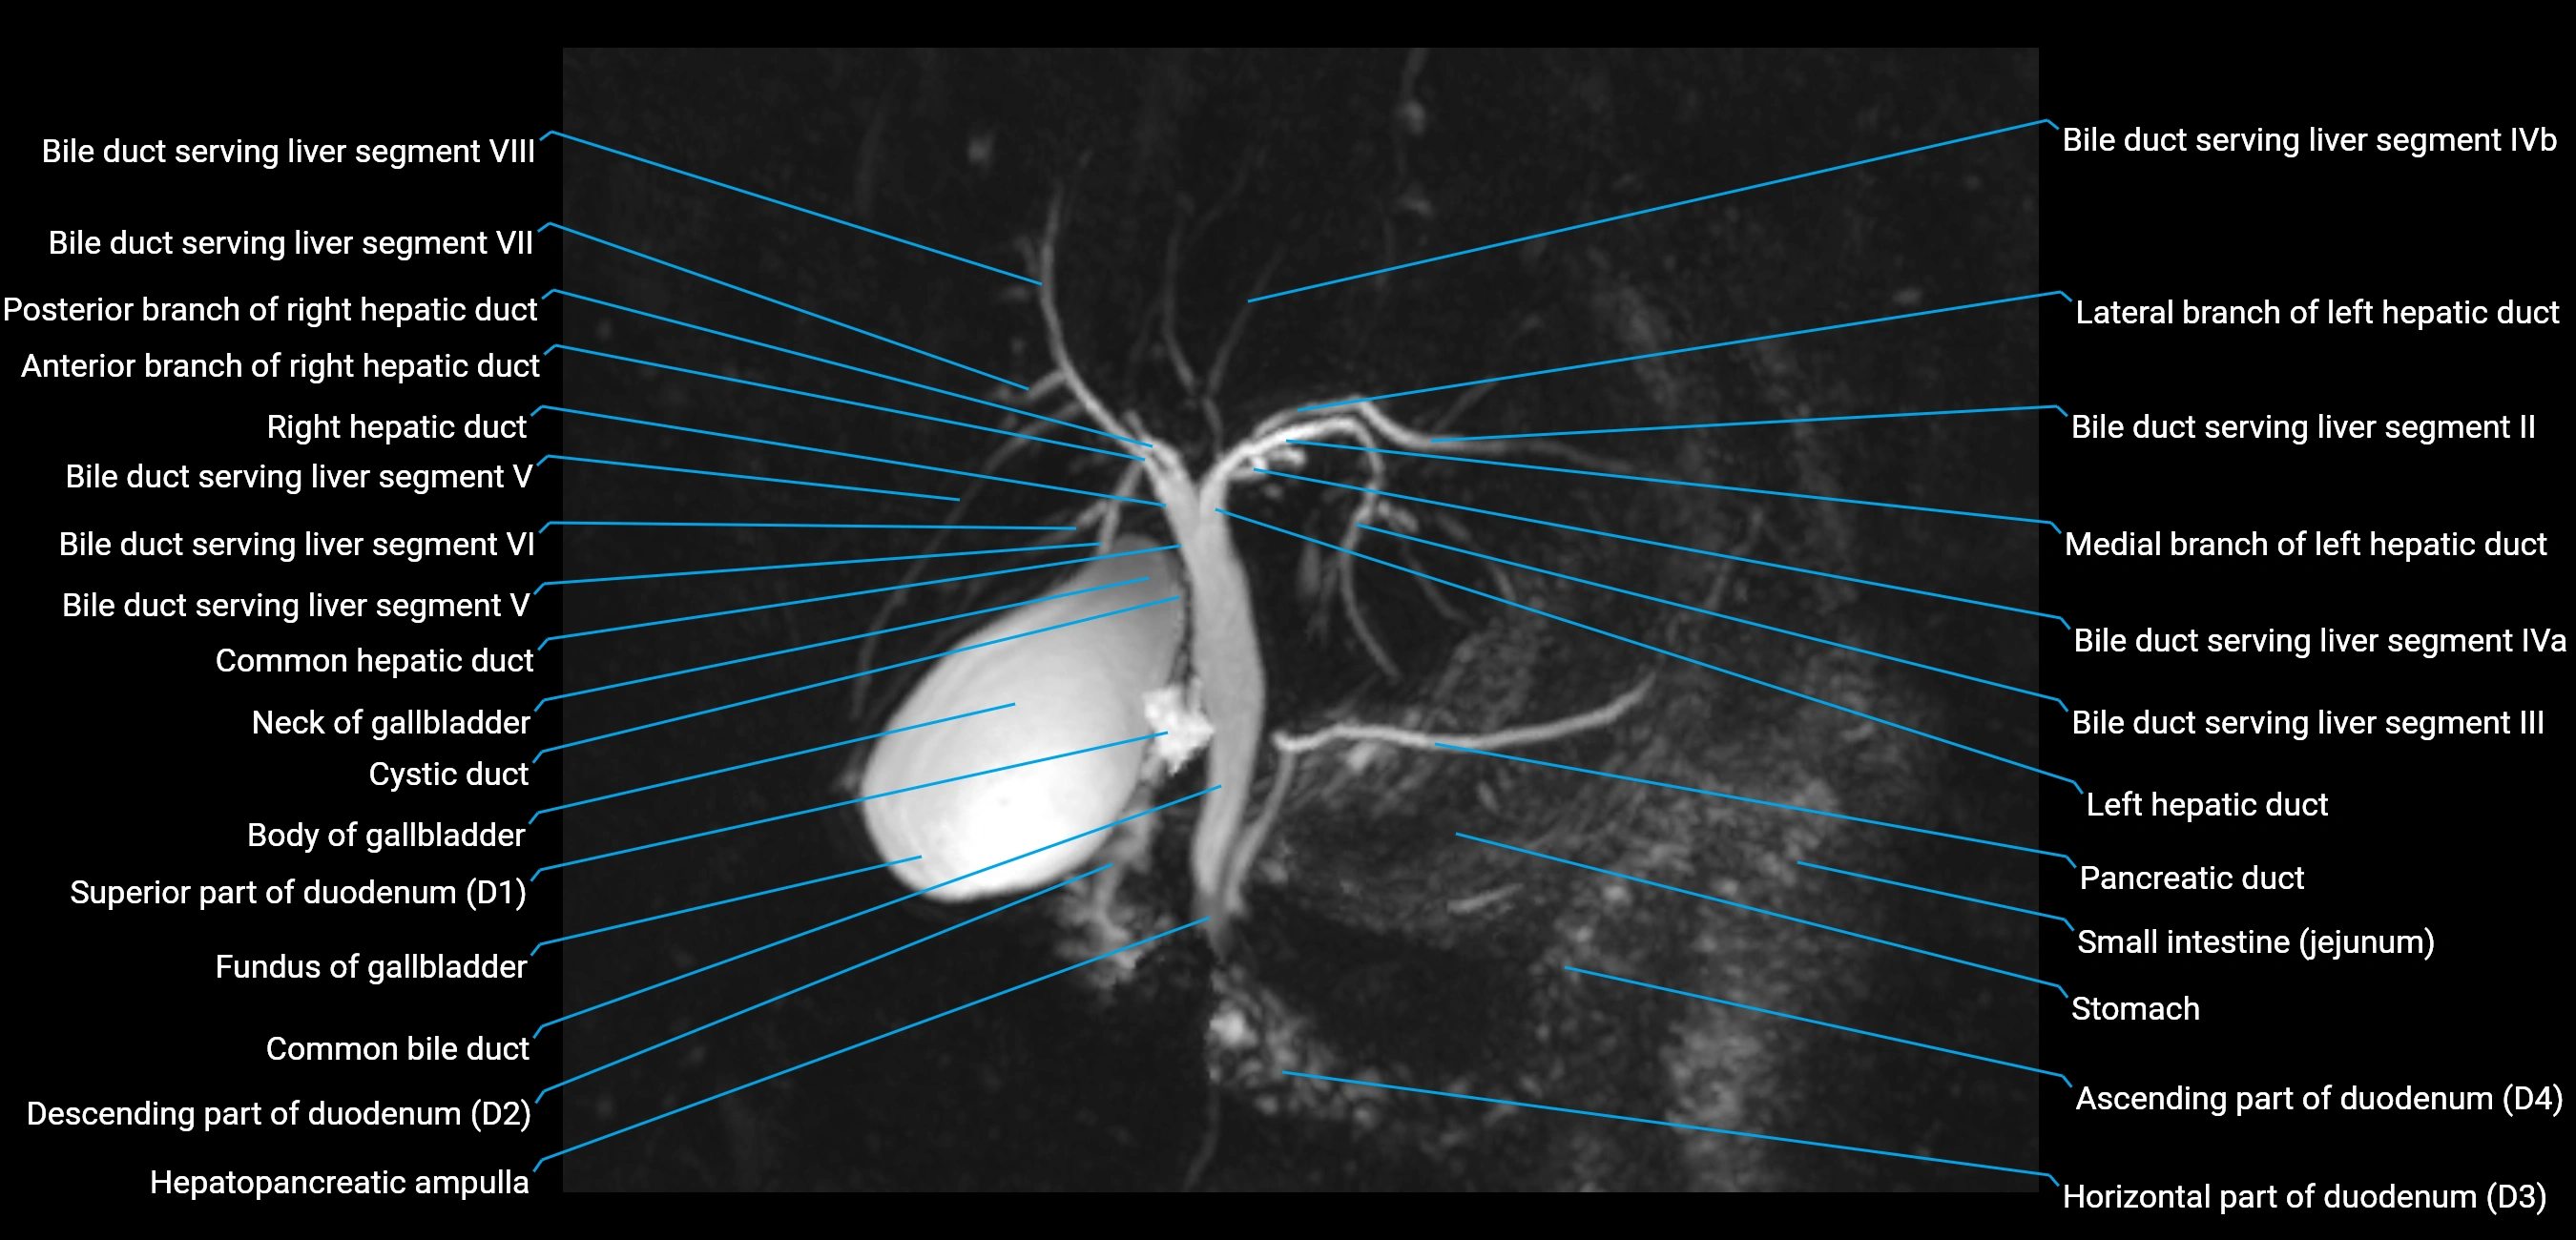

T2 TSE Fat-Saturated 3D (MRCP sequence):

• Duct visualized as a continuous bright tubular structure joining or parallel to the main pancreatic duct

• Allows 3D reconstruction of ductal anatomy and variants

• Excellent for diagnosis of pancreas divisum

Thick-slab T2 Fat-Saturated HASTE:

• Shows the accessory duct as part of the biliary–pancreatic system in a projectional image

• Highlights communication with main pancreatic duct and opening into the minor papilla

• Filling defects (stones, strictures) seen as dark spots within bright fluid

MRI image

image